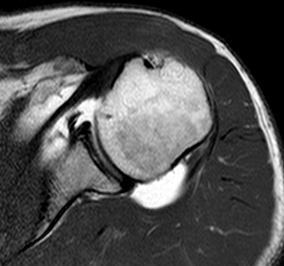

The normal shoulder has several layers.These layers mean that the shoulder joint is several centimeters below the skin. Swelling in the shoulder is not easily seen unless it is very severe.

Deep to the deltoid run muscles from the shoulder blade attaching to the top of the humerus just at the edge of the joint. These muscles are known as the rotator cuff. They form a near continuous attachment to the bone so an injury to the tendon (the white sinewy part of the muscle that attaches to the bone) of one muscle often extends into its neighbouring rotator cuff muscle.

Deep to the rotator cuff lies the deepest layer of soft tissue, the joint capsule. The capsule is a thin but strong fibrous layer that is supple enough to allow full movement but strong enough to stop the shoulder dislocating. It is inflammation in the joint capsule which causes the capsule to stiffen reducing movement causing the symptoms of a frozen shoulder. At the opposite extreme tearing of the capsular attachment to bone is what allows shoulders to dislocate.

Beneath all these layers lie the cartilage covered bones of the shoulder joint formed by the humeral head (top of the humerus) and the glenoid (the oval joint surface of the scapula). Arthritis in the bones of the shoulder joint results in loss of the white shiny and smooth articular cartilage leaving the much rougher bones directly in contact with each other.